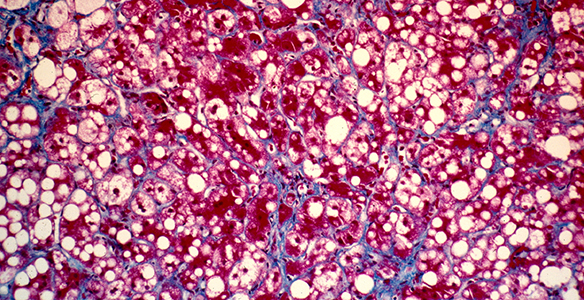

Die Leber ist die Entgiftungszentrale und größte Drüse des Menschen. Sie ist zentrales Stoffwechsel- sowie Speicherorgan und für das Immunsystem von übergeordneter Bedeutung. Die Behandlung von Lebererkrankungen bzw. Lebertumoren ist dementsprechend komplex und erfordert eine enge, fächerübergreifende Zusammenarbeit. Die Innsbrucker Univ.-Kliniken weisen dazu eine hohe Expertise auf diesem Gebiet auf. Im Leber Centrum Innsbruck (LCI) werden modernste Therapien, welche auf den einzelnen Patienten maßgeschneidert sind, angeboten. Unter anderem umfassen diese:

- Hepatitis C: dank hochwirksamer neuer Virustatika hat die Hepatitis C größtenteils ihre schweren Folgen, die irreversible Leberzirrhose verloren. -> Universitätsklinik für Innere Medizin I

- Leberresektion: Am Leber Centrum Innsbruck wird das gesamte Spektrum der operativen Entfernung von Lebertumoren bzw. Lebermetastasen angeboten. Die chirurgische Therapie wird vorab in gemeinsamen Tumorkonferenzen mit allen anderen beteiligten Disziplinen (z.B. Onkologie, Gastroenterologie, Radiologie, Radiotherapie, Pathologie, Anästhesie) individuell auf jeden Patienten abgestimmt, um ein bestmögliches Resultat zu erzielen. Eine besondere Bedeutung kommt hierbei der Planung von mehrstufigen Therapien zu, bei denen z.B. mehrzeitige chirurgische Eingriffe und/oder Radiofrequenzablationen mit systemischen Therapien (Chemotherapie) kombiniert werden für ein optimales Tumoransprechen. ->Univ.-Klinik für Visceral-, Transplantations- und Thoraxchirurgie.